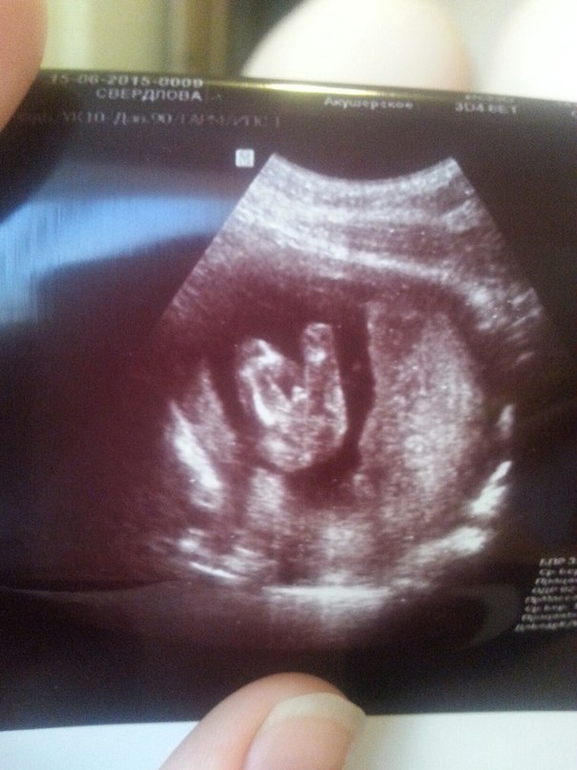

Хочу поделиться с Вами нашей огромной радостью! У нас будет СЫНУЛИК! Свердлов Михаил Александрович! Уже даже и имя есть))) Муж рад до безумия! Сказал вот такую фразу на УЗИ: "Это непередаваемо! Вот он, тот момент, когда рад увидеть бубенцы!

15.06.15 - День, когда нам сообщили, что у нас будет мальчик. Что есть кому продолжить род Свердловых!

И вот, самое главное, после ЖК мы направились в платную поликлинику, где я записалась на прием (Вита-Медикус). Коленки дрожали, живот сводило, руки тряслись))) Мало того что я снова увижу мое маленькое сокровище, так еще и муж будет рядом! Кабинет оказался потрясающим. Мы смотрели на кроху на большом дисплее, муж держал меня все время за мою ногу)))) Врач тоже супер супер супер, теперь если платно куда идти - только к ней! (даже показала нам немного в 3D малыша, хоть мы и не просили..и фотку сделала! Такой монстрик конечно)))) Малыш все время крутился, вертелся, ручками махал, ножками болтал, даже узистка засмеялась один раз,когда наша юла в очередной раз завертелась,убегая от нас)) Под конец мне сделали Узи с..другого ракурса) Чтобы проверить мою плаценту. В общем, она поднялась!!! ДА! Уже 1.7 см от зева, ничего не перекрывает, все хорошо, сказали что еще будет подниматься дальше! А на 3D медвежонок прям лежал как на перине на плаценте))) Забавно так

А еще нам сообщили что малыш пока опережает события:) КТР уже более 10см (10,46), крупненький, мозг тоже ого-го (ну вундеркинд! Не зря с ним и госы и диплом на отлично сдала!) - соответсвует 16нед.3дн, а сейчас у нас только 15.2.

А вот и бубенцы на фото

(попка внизу, ножки вверху, а посередине морковка!:)